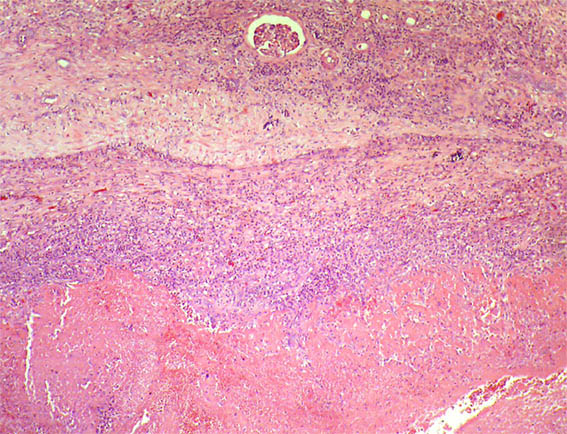

Figura 2. H&E, X40.

Figura 4. H&E, X40.